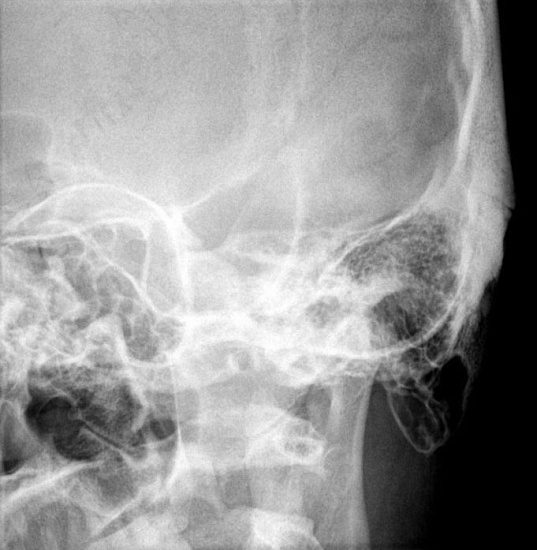

3. Рентгенография височных костей в осевой проекции (укладка по Майеру)

Прицельное исследование среднего уха, выполняется в одной проекции.

Показания для проведения исследования:

• изучение состояния среднего уха, в основном сосцевидной пещеры (антрума);

• определение поражения структур среднего уха при травмах (в случае продольного перелома пирамиды).